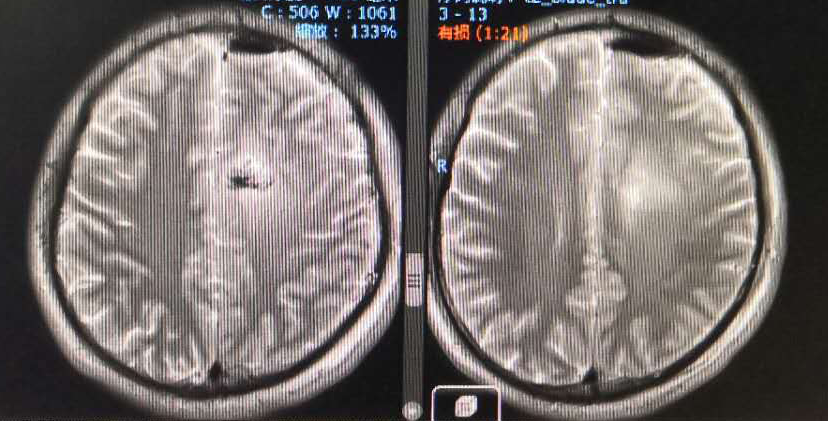

从术前核磁上看左侧额顶叶水肿范围较大,但是从增强上看似乎有强化,内囊前肢前上方有占位, Cho显示是升高的,考虑是肿瘤改变。

术后MRI显示术区水肿余无特殊

2020-01-06放疗后MRI

2020-4-23 MRI复查

复查MRI提示:局部病灶强化,PWI提示局部灌注有缺失,考虑病情进展,同时不除外假性进展,患者脑水肿范围较大。